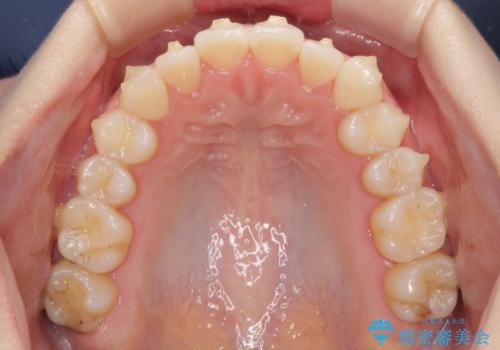

前歯のクロスバイトをインビザライン矯正で改善

- 前歯のデコボコと上下のクロスバイトを気にして来院された患者様です。

インビザラインを用い、IPR(歯と歯の間を削る)と歯列全体を拡大させることで、歯並びを整えていくこととしました。

上の前歯が下の前歯を乗り越える際、奥歯がほとんど咬めない時期があり、乗り越えた後も、インビザライン特有の奥歯の咬みにくさが続きました。

咬み合わせ改善のために治療期間を要しましたが、最終的に奥歯はしっかりと咬めるようになりました。